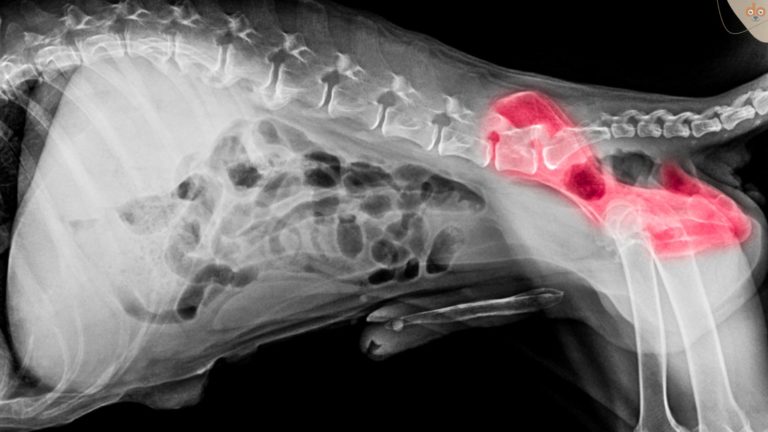

Ob ein Hund an Hüftgelenk-Dysplasie leidet, ist durch eine Röntgenaufnahme feststellbar. Der FCI unterteilt die Röntgenuntersuchung in zwei und den Schweregrad einer Hüftgelenk-Dysplasie nochmals in drei Kategorien. Bei den ersten beiden Kategorien gibt es keinen Hinweis auf Hüftgelenk-Dysplasie bzw. die Gelenke gelten als “fast normal”. Die drei weiteren Kategorien untermauern die Diagnose Hüftgelenk-Dysplasie und ordnen sie als – leichtgradig, – mittelgradig oder – schwer ein.